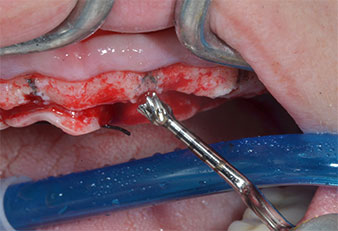

Пиезоелектрически инструмент с диамантено покритие с форма на пламък (Piezomed I1) e използван за маркиране на позициите на имплантите и за пилотна подготовка (Фиг. 3). Препарацията беше извършена с внимателни вертикални движения, с намалена мощност, пълна иригация и лек натиск (под 300 g) След това се приложи пилотен инструмент (Piezomed I2A/ I2P) за първоначално увеличение на диаметъра на имплантното ложе с 2 mm (Фиг. 4), последвано от 3 mm разширение (Фиг. 5)

В случай на твърда кост, цялата поредица от инструменти, включително междинните инструменти Piezomed Z25P и Z35P, трябва да се използват за разширяване на остеотомиите.

Те също така са предназначени за подготовка в близост до синусовата мембрана във връзка с вътрешни аугметационни процедури или когато има по-малко от 4 mm остатъчна височина на костта.

В настоящия случай инструменти Z25P и Z35P не са използвани поради сравнително меката задна кост, която лесно се обработва с I3A/I3P.

Поради сравнително твърдата кост (D2) в тази област, 10-милиметровото имплантно ложе в позиции 11 и 21 беше завършено с ротационен дрил с диаметър 4 mm в комбинация с W&H хирургичен обратен наконечник WS-75 L, W&H имплантологичен мотор Implantmed и опционалния W&H Osstell ISQ модул. За разлика от това, благодарение на меката кост, дисталните зони се подготвят до окончателен диаметър 3 mm, използвайки накрайник за Piezomed I3P. Имплантите най-накрая са поставени трансгингивално, за да остеоинтегрират за три месеца (Фиг. 6-10). Съществуващата протеза се фиксира на четирите временни импланта (Фиг. 8).